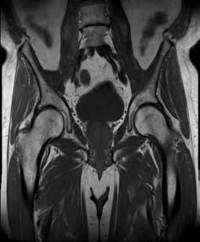

A 75-year-old woman sustains a displaced femoral neck fracture after a mechanical fall. Which of the following is the predominant blood supply to the femoral head that is at risk of disruption in this injury?

The predominant blood supply to the adult femoral head is provided by the lateral epiphyseal artery, which is the terminal branch of the medial femoral circumflex artery (MFCA). This runs along the posterosuperior aspect of the femoral neck and is frequently disrupted in displaced femoral neck fractures, leading to a high risk of avascular necrosis.